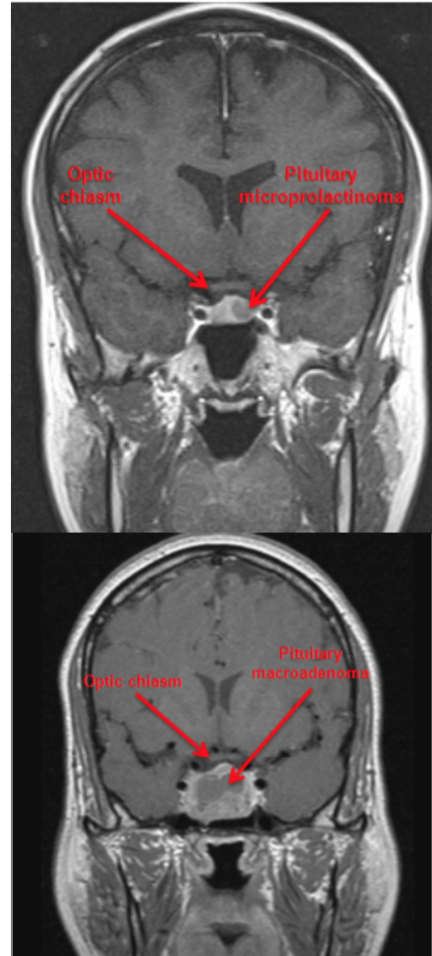

Microadenomas: < 1 cm

Macroadenomas: > 1 cm

MRI – esp if visual defect is noted